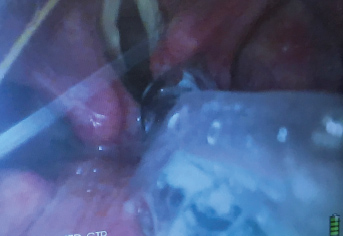

When the trachea is extremely tortuous and it has been impossible to slide a standard ETT over the FIS into the trachea, a spirally reinforced or "armored" ETT can be used. This type of ETT will follow the FIS more easily because it has less internal rigidity and therefore conforms more readily to unusual tortuous airway anatomy. The Parker flex tip endotracheal tube has also been shown to pass more easily over a fiberscope than a conventional ETT [37]. The ETT that is provided with the intubating LMA is a soft wire-reinforced silicon tube and its tip conforms readily to airway anatomy and is also excellent at sliding easily over a flexible bronchoscope (Figure 3, Figure 4 and Figure 5) [38].

Figure 3: The vocal cords are visualized with the video-laryngoscope (VL) while the flexible intubation scope (FIS) is used to steer the endotracheal tube (ETT) into the trachea.